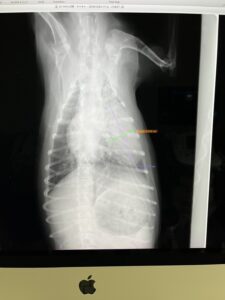

チャチャちゃん 結果

⭕️肺腫瘍 相変わらず大きい

⭕️胆石あり ⭕️中性脂肪高い

⭕️左脚 歩行時傾き 立ち上がり弱い

馬尾症候群

⭕️腰椎 1と2異常

⭕️肘たこ 良性

⭕️顔面チック症

2025年 年内で検診出来ました。